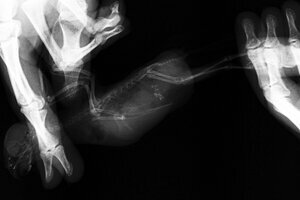

Птичка на диете похудела и стала весить 52 грамма. Взяла вот сейчас в руки, пощупала - пузико стало мягким. А вот что с грудкой?? :shock:

[​IMG]

Sigrilin, что значит плохая?? Обычно нет этого тёмного..сосудиков или что это.

Из-за чего это "что-то"? Что делать? Насколько опасно? Это не от ограничения количества корма?

Галчонок, 52 гр - это много для волнушечки. Будем надеяться, что это жир. Сделай фото, чтобы было видно эту область еще лучше.

Галчонок, место не характерное, эо не зоб, что оставляет надежду на жир... или достаточно приличная липома...